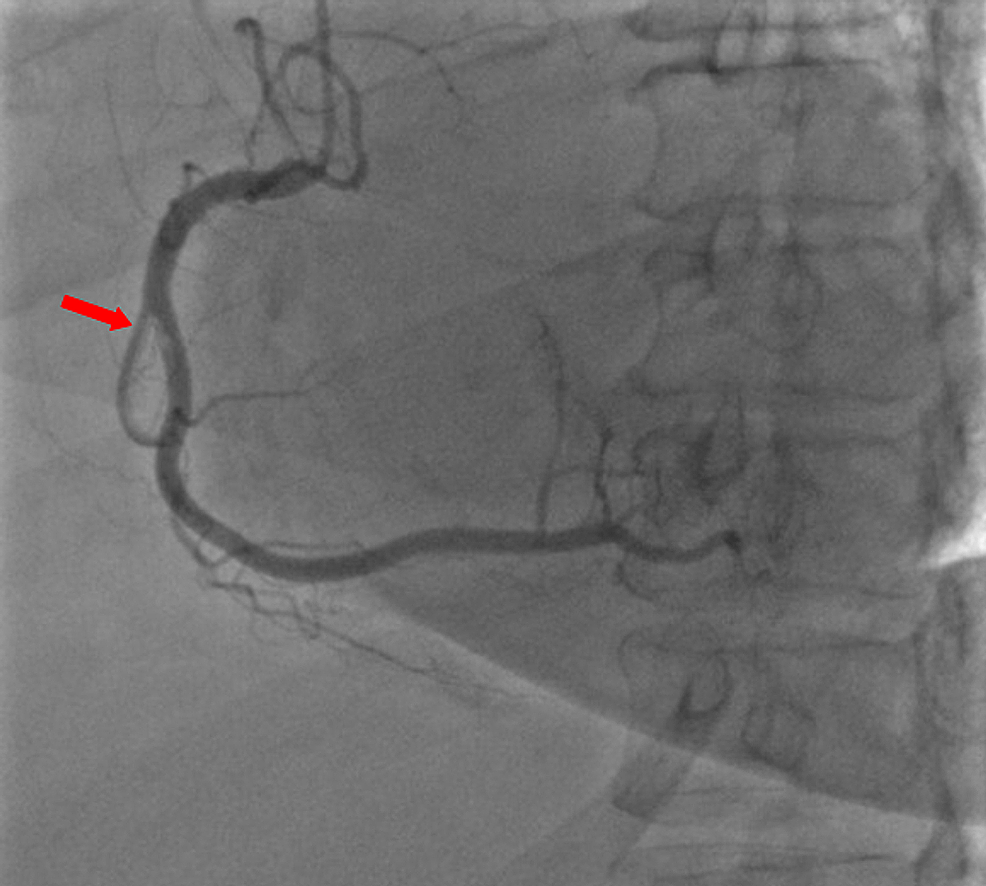

A 59-year-old woman was admitted to the emergency department with sudden onset of chest pain for five hours. She had hypertension (treated with β-blockers) as a cardiovascular risk factor. She was diagnosed with advanced non-small-cell lung cancer with liver metastases one month previously. The patient was not considered for surgical resection, she was scheduled for chemotherapy, and, consequently, no antineoplastic treatment had been initiated yet. Prophylactic anticoagulation was not indicated On clinical examination, her blood pressure was 150/90 mmHg with a pulse of 100 beats per minute, oxygen saturation of 95%, and normal heart sounds. The 12-lead electrocardiogram showed sinus rhythm with a heart rate of 102 beats for minutes and ST-segment elevation in all leads except aVR where ST-segment depression was noted (Figure 1). Her laboratory test results revealed a baseline troponin T level of 1212 ng/ml (normal range < 26 ng/ml). Also, the echocardiography findings revealed akinetic walls from the mid to apical septum and anterior and inferior walls. The ejection fraction was estimated to be 39%. Therapy was started with clopidogrel, aspirin, and low-molecular-weight heparin. The patient underwent a coronary angiogram from the right radial approach, which revealed the presence of an extended thrombus in the left anterior descending artery (LAD), and another thrombus was found in the second segment of the right coronary artery (RCA) with thrombolysis in myocardial ischemia (TIMI) III flow and without any atherosclerotic lesions in the coronary artery tree (Figure 2 and Figure 3), therefore, balloon angioplasty and/or stent placement was not considered. The patient was taken to the coronary care unit (CCU) and tirofiban infusion was administered for a period of 48 hours. In view of persistent breathlessness, pulmonary embolism was suspected. There were no symptoms or clinical signs suggestive of deep venous thrombosis. A computed tomographic pulmonary angiography was performed and showed a distal pulmonary embolism (Figure 4). The patient was discharged on acenocoumarol to be followed as an outpatient. At her 45 days follow-up, she did not report any episode of chest pain, bleeding, as well as any thrombotic events.

Malignancy is a recognized risk factor for deep vein thrombosis, pulmonary embolism, and even arterial thromboembolism, including peripheral thrombosis, stroke, and myocardial infarction [3]. Thrombosis represents the second most common cause of death in cancer patients [4]. Several determinants are considered to participate in hypercoagulability in malignancy. The secretion of pro-inflammatory cytokines and pro-coagulants from neoplastic cells causes endothelial damage in many vascular territories. The consequence is upraised vascular permeability for platelet-activating factors and tissue factors, decreased inhibitors of coag­ulation, and impaired fibrinolysis, which increase the risk of thrombosis [5-6]. The present case describes a rare case of intracoronary thrombosis in a 59-year-old woman recently diagnosed with lung cancer. The coronary angiography had not revealed any significant coronary stenosis in the entire coronary artery tree. It is reasonable that the hypercoagulable state of cancer was responsible for intracoronary thrombosis. This is consistent with a few previously reported cases.